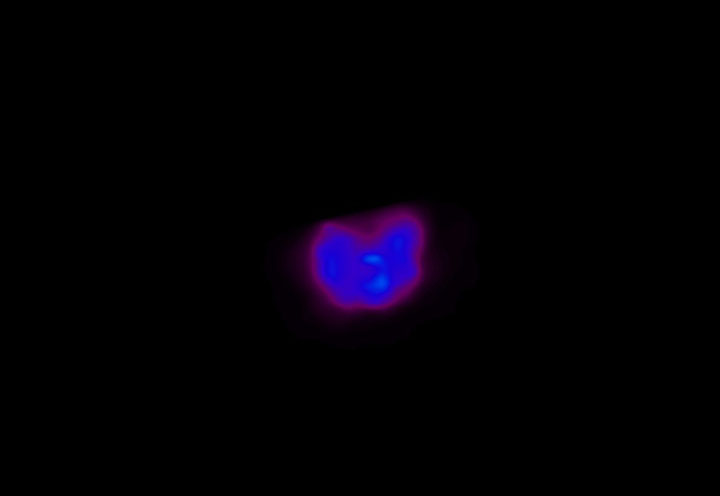

Head / Case4 : Amyloid

Axial

Courtesy : Kindai University Hospital

- Injected dose: 3.21 MBq/kg, 18F-Flutemetamol

- Uptake time: 100 minutes

- Scan time: 20 minutes